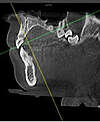

- La position de certaines structures anatomiques avant chirurgie,

- La précision lors des sinus-lift,

- La pose d'implants,